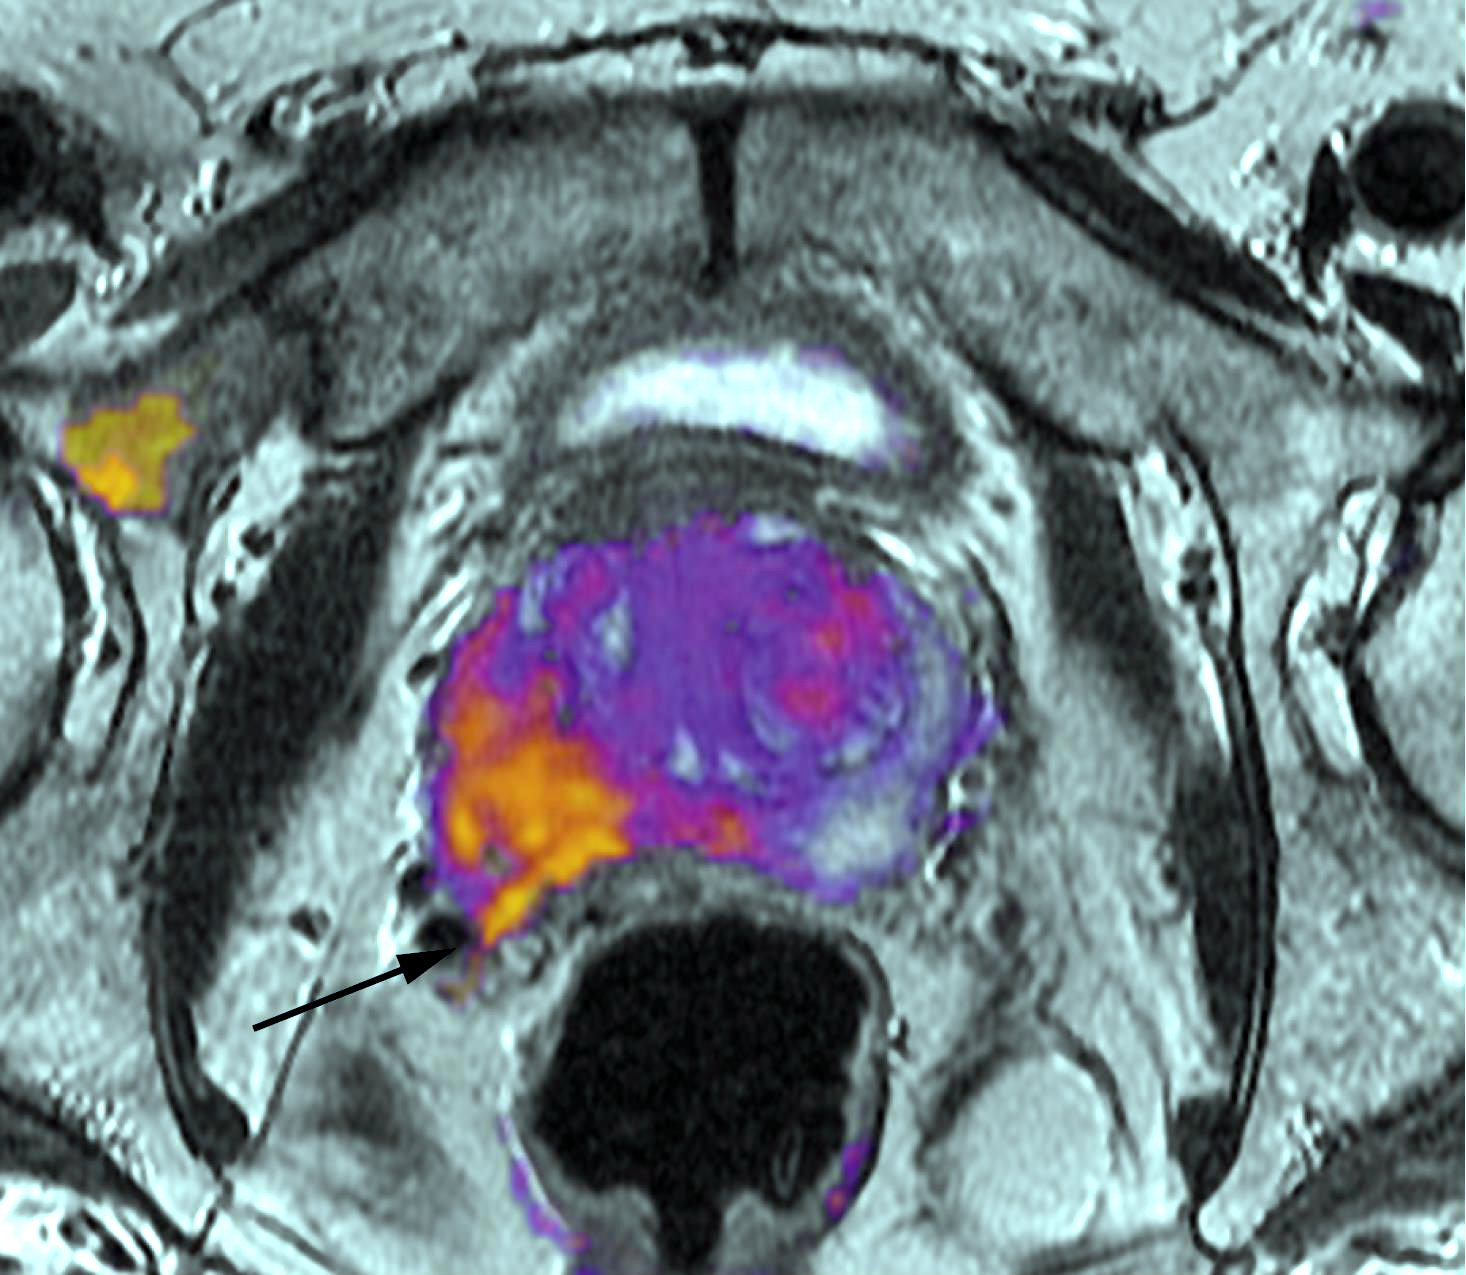

El mayor consumo de alcohol durante la juventud se asocia con el diagnóstico posterior de cáncer de próstata. Cancer Prevention Research, 23 de agosto de 2018

Tendencias en EEUU del rastreo con PSA y de la mortalidad por cáncer de próstata

Junto con la reducción del uso del PSA a partir de 2007, se niveló el descenso previo de la mortalidad por cáncer de próstata, con aumento de diagnósticos en etapa avanzada. Cancer, 22 de mayo de 2018

Rastreo con PSA entre los 55 y 69 años: una decisión del paciente

En una revisión de su planteo de 2012, la United States Preventive Services Task Force recomienda a los médicos transmitir los pros y contras del procedimiento para facilitar la decisión individual. Sigue vigente la posición de no hacer rastreo con PSA en mayores de 70 años. USPSTF, mayo de 2018